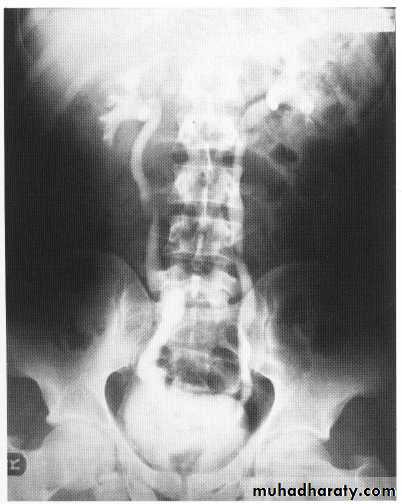

horse shoe kid

This is a common renal anomaly affecting

1/400 live births, with a 2 to I male predilection. In utero contact between the metanephric tissue of the developing kidneys results in a midline connection (isthmus) between the lower poles